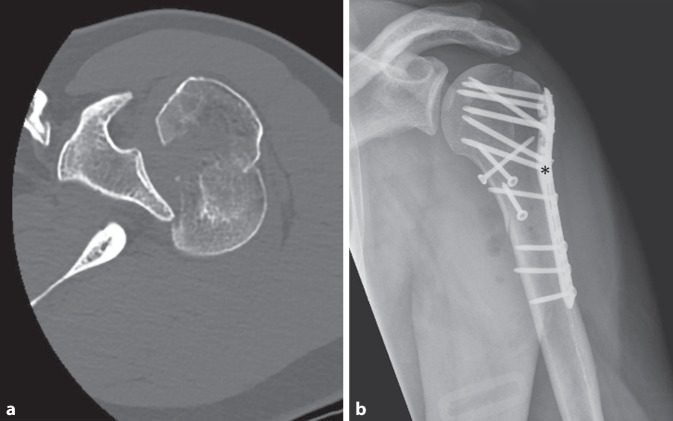

Abstract Image